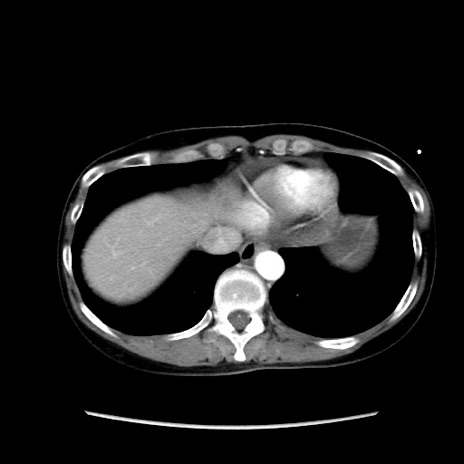

冠状断像

【症例】40歳代 女性

【主訴】上腹部痛、嘔気・嘔吐

【現病歴】約9時間前頃から急に上腹部痛、嘔気、嘔吐が出現。改善しないため救急要請。

【既往歴】子宮頚癌(広汎子宮全摘術、放射線療法)、腸閉塞

【身体所見】腹部:平坦、軟、腸雑音亢進、上腹部を中心に腹部全体に圧痛あり。

【データ】WBC 8400、CRP 0.03